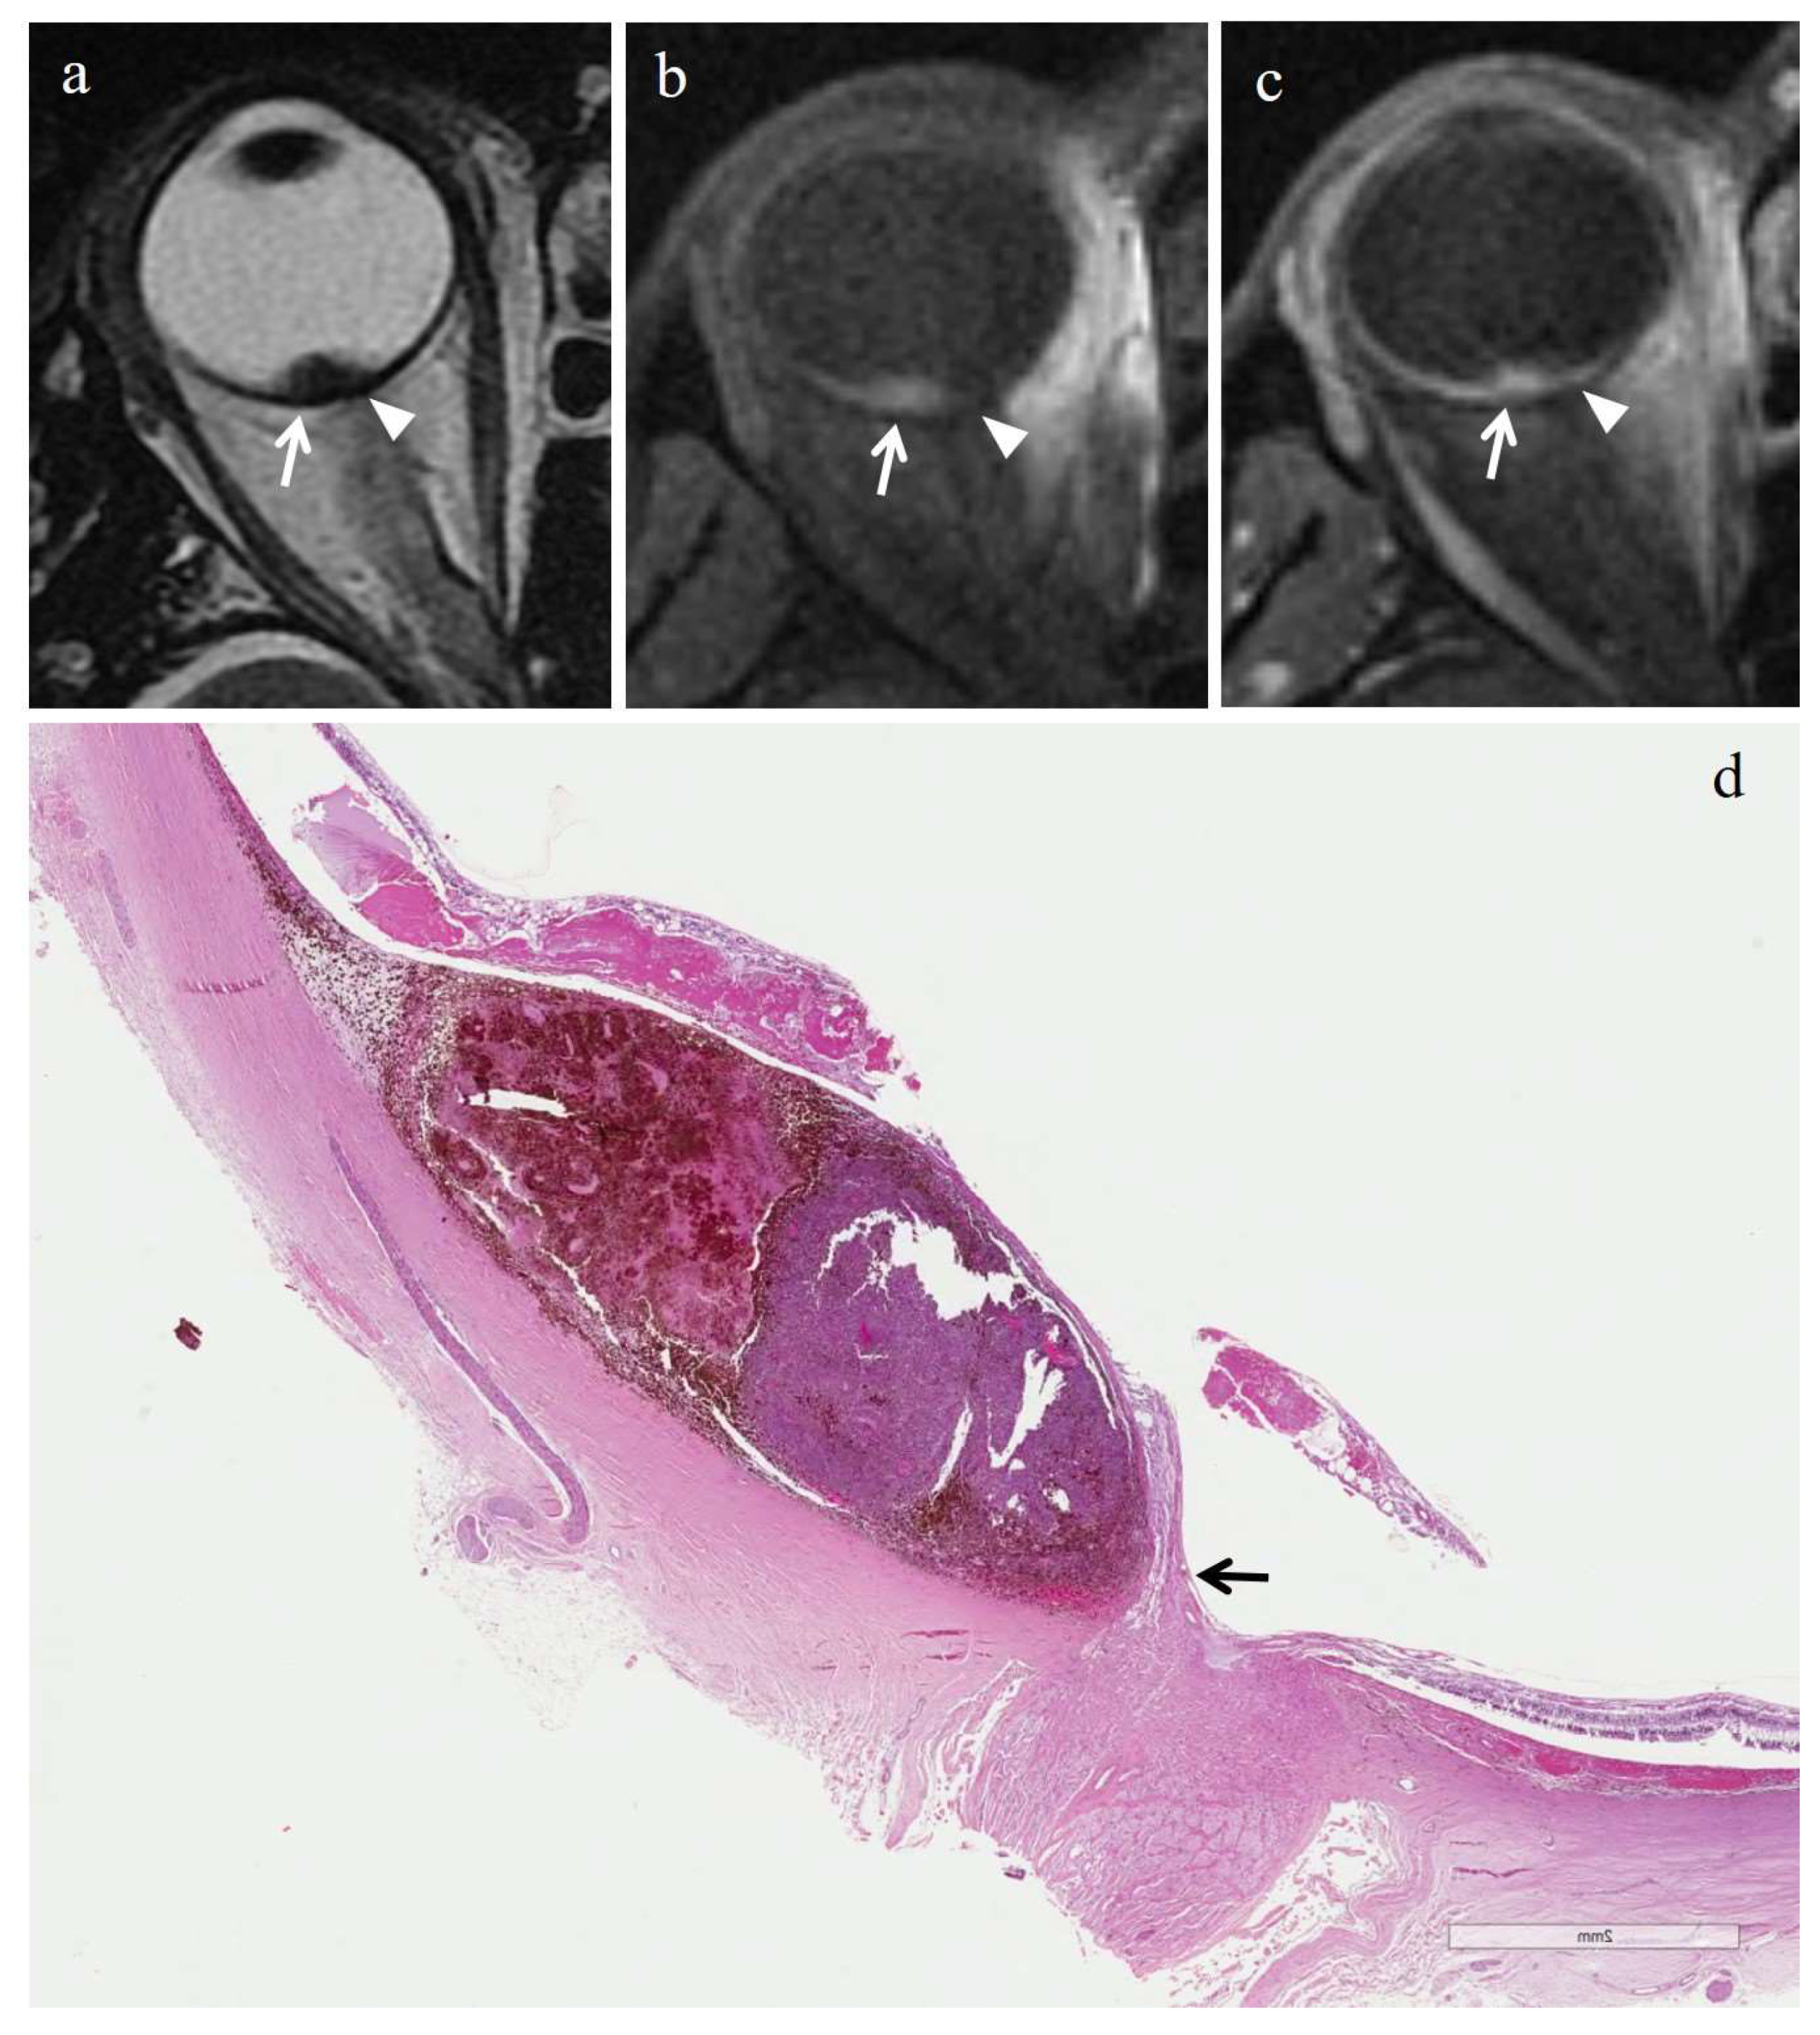

3.2.2. Histopathologic Findings in the Control Group

3.3.2. MRI Findings in the Control Group

| Patient | Histologic Type | Degree of Pigmentation | Degree of Necrosis | Necrotic Pattern |

|---|---|---|---|---|

| 1 | Epithelioid cell | Pigmented | Grade I | Multiple foci- hemorrhagic/coagulative-type, tumor necrosis |

| 2 | Epithelioid cell | Poorly pigmented | Grade I | Multiple foci- hemorrhagic/coagulative-type, tumor necrosis |

| 3 | Spindle cell | Pigmented | Grade II | Multiple foci tumor necrosis |

| 4 | Mixed cell type | Pigmented | Grade I | Multiple foci tumor necrosis |

| 5 | Spindle cell | Pigmented | Grade I | Multiple foci- hemorrhagic/coagulative-type, tumor necrosis |

| 6 | Mixed cell type | Poorly pigmented | Grade I | Multiple foci- hemorrhagic/coagulative-type |

| Patient | T2 | T1 | Gd-T1 | DWI | ADC × 10−3 mm2/s ** |

|---|---|---|---|---|---|

| 1 | - | - | - | - | 1.04 |

| 2 | - | - | - | - | 1.22 |

| 3 | - | - | - | - | 0.63 |

| 4 | - | - | - | - | 0.78 |

| 5 | - | - | - | - | 1.05 |

| 6 | Hyperintense | Hypointense | No enhancement | No restriction | 0.80 |